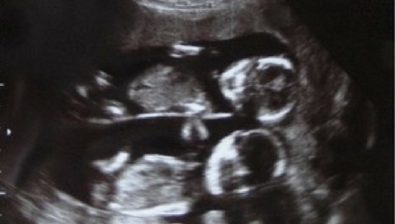

17 Weeks Pregnant: With Twins

Coming in at 17 weeks pregnant with twins or multiples, you’re likely way ahead of singletons moms in many ways.

There’s a good chance that your skin has become itchier as it stretches to accommodate a rapidly growing belly. That’s not going to slow down any time soon, so stock up on lotion to ease the itchiness.

Also, if you haven’t lost sight of your toes, you might want to start saying your goodbyes now.

Being pregnant with more than one baby means you lose sight of the things under your belly more quickly than other moms.